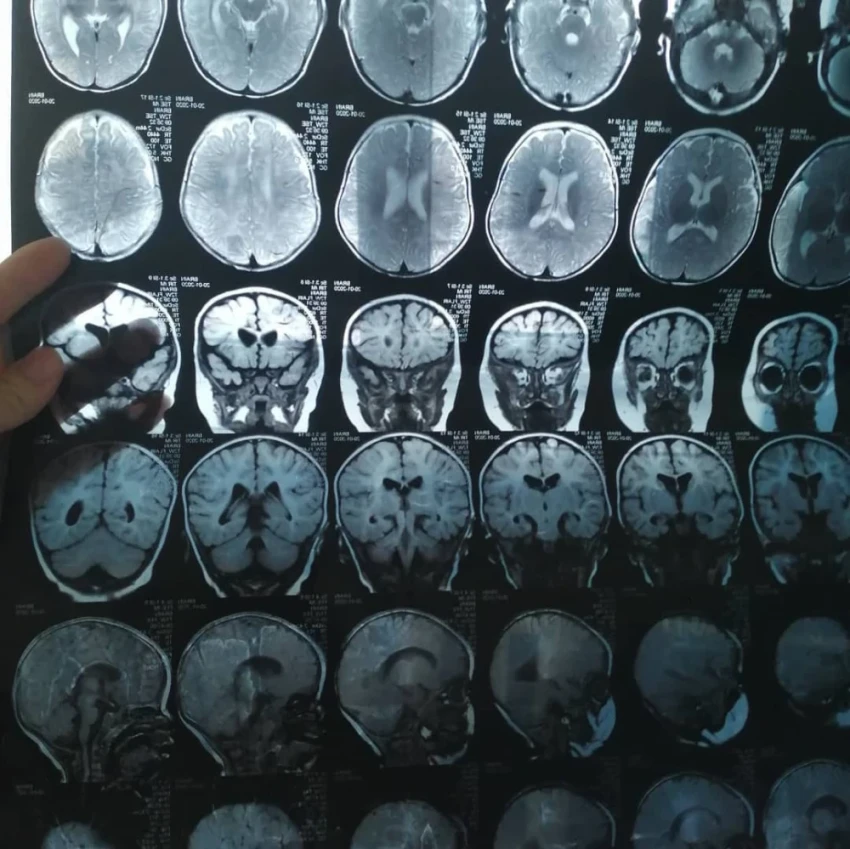

"Айкол появилась на свет недоношенной, и диагноз ДЦП был поставлен сразу после рождения. В начале муж активно помогал мне в уходе за ней, однако со временем его отношение изменилось, и он покинул нас. Я думаю, он так и не смог смириться с болезнью нашей дочери", - рассказывает Бегимай.

У дочери Бегимай ряд сложных диагнозов, ей нужна помощь.

Айкол уже перенесла две операции в Бишкеке, направленные на исправление двусторонней деформации голеностопного сустава, но, к сожалению, результаты оказались неудовлетворительными.